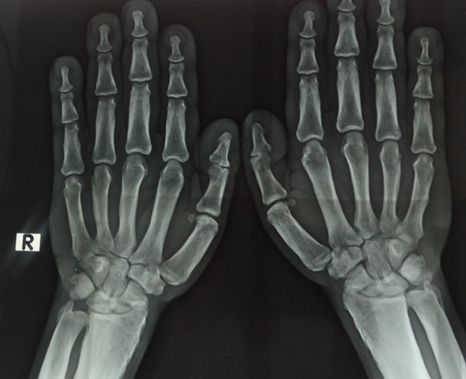

On cutaneous examination, the patient had thickened and moist fingers and toes, digital clubbing, and deep creases on the forehead and scalp (Figures 16). Initially, acromegaly was considered; however, the absence of facial features such as an enlarged nose, chin, and tongue made this diagnosis unlikely. Radiographic imaging of the hands and feet showed periostosis of the fingers and toes, confirming pachydermoperiostosis (PDP).

Figure 4 Hand X-ray revealing hyperostosis of all fingers, radius, and ulna.